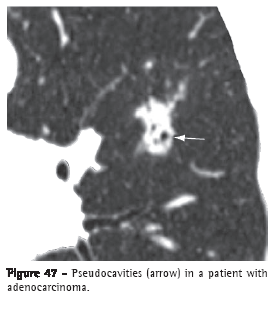

Pseudocavity (pseudocavidade)

A pseudocavity is a round or oval-shaped area of low attenuation in nodules, pulmonary masses or areas of consolidation within a portion of preserved pulmonary parenchyma, within dilated or normal bronchi or (as an area of emphysema) within a lesion (Figure 47). Pseudocavities generally measure less than 1 cm in diameter. They can be seen in patients with adenocarcinoma, bronchioloalveolar carcinoma or pneumonia.(7,72)